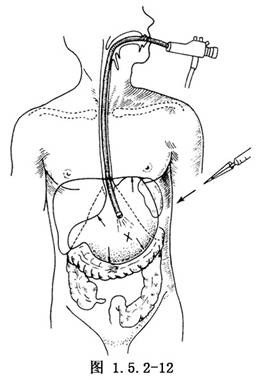

操作时,患者口咽部喷雾局部麻醉,仰卧于手术台上,头侧略抬高,将纤维胃镜经口插入胃腔。上腹部常规消毒,铺消毒巾。内镜医师通过胃镜向胃内充气使胃扩张、结肠下移、胃前壁紧靠前腹壁,直视下将胃镜端抵住胃前壁,同时将房间灯光转暗,观察上腹部由胃镜透照出的光亮区。这一部位通常是在肋缘与脐之间的中点(图1.5.2-12),消瘦病人从该处可以触到胃镜端。在透光处做一个标记,将胃镜退回少许,检查一下选点是否合适。于标记处做局部麻醉,切开皮肤长1cm,用16号斜面导管针经切口穿刺,通过腹壁及胃壁进入胃腔。同时内镜医师应观察到穿入胃腔的针头。这些步骤应迅速完成,以减少胃从腹壁向后移的机会。拔除穿刺针芯从外套管内插入一粗的不吸收线或尼龙缝线。内镜医师通过胃镜插入一息肉圈套器将不吸收线套住,然后拉住不吸收线连同胃镜一起从病人口腔内退出(图1.5.2-13)。将带有内衬垫的de Pezzer导管(图1.5.2-14)或PEG专用导管牢牢固定在口腔侧长线上。导管端必须呈锥形,必要时可做一锥状塑料套管套住de Pezzer导管的开口端。长线及导管端涂上无菌水溶性润滑剂将腹侧端长线轻柔、稳定持续地向外牵拉使锥形导管被牵拉拖入食管进入胃腔并由腹壁穿刺孔拖出(图1.5.2-15)。再次插入胃镜确认置入的导管位置是否正确并及时加以调整。腹壁外放置外衬垫或圈状物,将导管与衬垫固定在皮肤上,注意松紧要适度,不宜过紧,以防皮肤压迫坏死(图1.5.2-16)。4周后,胃前壁已与腹壁牢固附着,可以改用硅胶代用品导管并可以装配一合适的堵塞器装置(图1.5.2-17,1.5.2-18)。